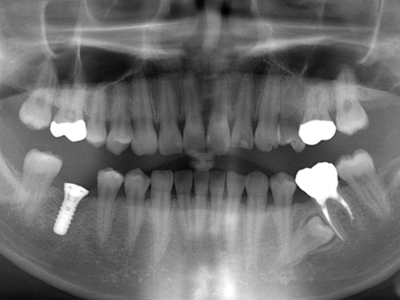

11. インプラント埋入後X線パノラマ

右下6番部のインプラント埋入後のX線写真です

9. 施術前X線パノラマ

22歳の可愛らしい女性で、この都心で一生懸命働いて自活なさっている方です。インプラントは当医院では約40万円かかります。キャンセルも多く、治療運営上もコントロールできるかどうか不安でしたが、インプラントの説明をこの段階から始めました。当初はこのままでも良いなどと自虐的なこともおっしゃっていましたが、説明を3ヶ月行い、納得していただけました。